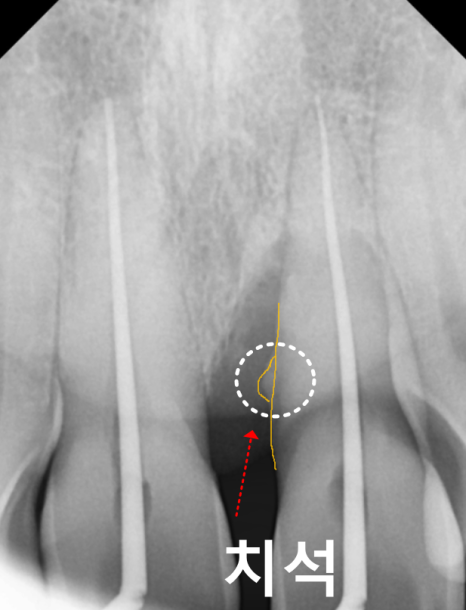

치석으로 인해 내려간 잇몸

치아와 잇몸 사이 틈새에 치석이 쌓이면서

잇몸에 염증이 시작되고,

아래 치조골(잇몸뼈)을 녹이면서

잇몸도 따라 내려가게 됩니다.

정확한 상태 확인을 위해 엑스레이 촬영과 검사를 진행한 결과,

치석으로 인해 잇몸병이 진행되면서

잇몸뼈가 일부 녹아 있는 상태였습니다.